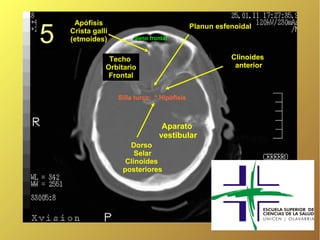

Apófisis 5 Planun esfenoidal Crista galli (etmoides) Seno frontal Techo Clinoides Orbitario anterior Frontal Silla turca: * Hipófisis Aparato vestibular Dorso Selar Clinoides posteriores